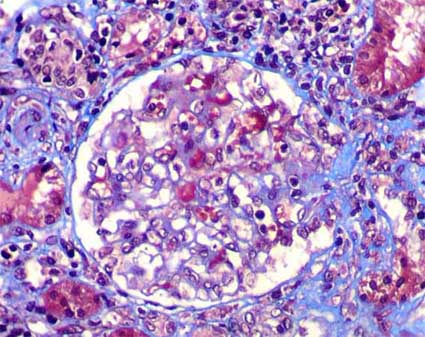

Figura 3. En algunos casos de nefropatía IgA encontraremos lesiones glomerulares esclerosante segmentarias como en esta biopsia de un hombre de 37 años con hematuria micro persistente. Estas lesiones pueden indicar un grado mayor de severidad de las alteraciones renales, pero, no necesariamente se correlacionan con la proteinuria o con la función renal. (Tricrómico de Masson, X400).

Figura 4. En este glomérulo además de hipercelularidad mesangial hay segmentos con hipercelularidad endocapilar, disminución de luces capilares y células inflamatorias. La flecha señala una pequeña semiluna epitelial circunscrita. (H&E, X400).